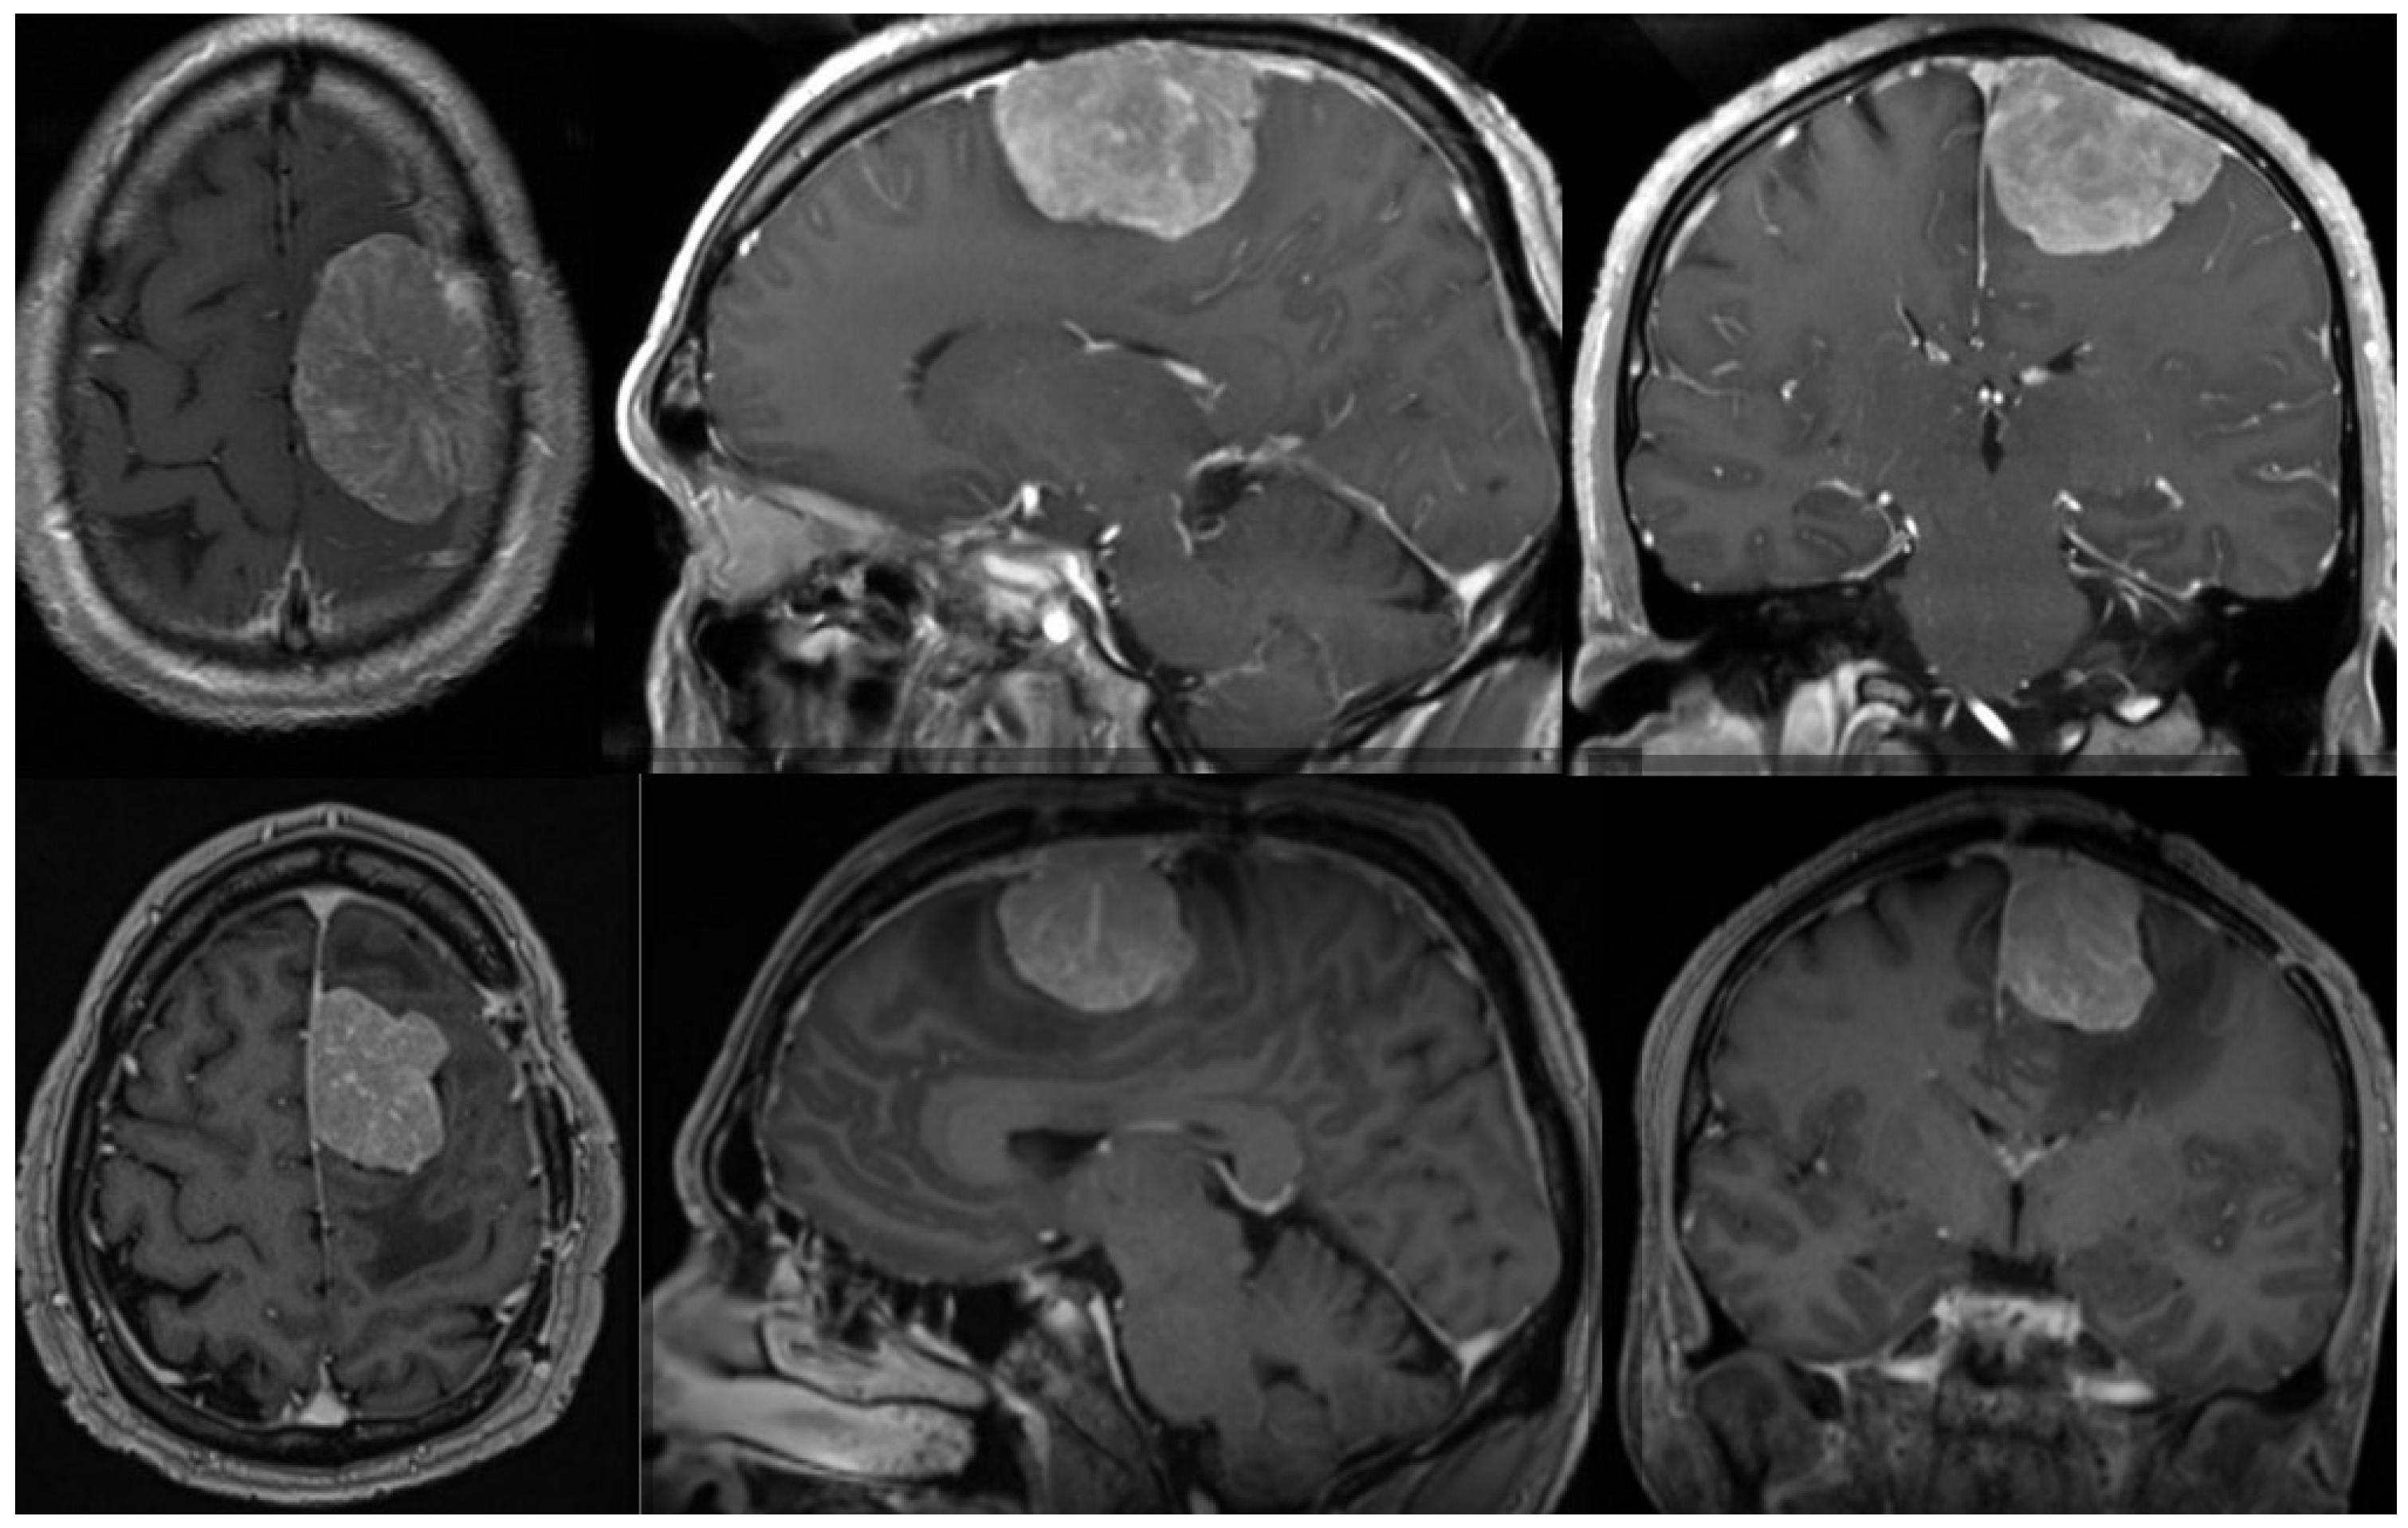

- Liang, Y.; Ning, B.; Hua, X.; Liang, Z.; Ye, J.; Yu, F.; Xu, Z.; Chen, J. Atypical meningioma: A retrospective analysis of six cases and literature review. Transl. Cancer Res. 2021, 10, 1509–1518. [Google Scholar] [CrossRef] [PubMed]

- Surov, A.; Gottschling, S.; Mawrin, C.; Prell, J.; Spielmann, R.P.; Wienke, A.; Fiedler, E. Diffusion-Weighted Imaging in Meningioma: Prediction of Tumor Grade and Association with Histopathological Parameters. Transl. Oncol. 2015, 8, 517–523. [Google Scholar] [CrossRef] [PubMed]

- Nagar, V.A.; Ye, J.R.; Ng, W.H.; Chan, Y.H.; Hui, F.; Lee, C.K.; Lim, C.C.T. Diffusion-Weighted MR Imaging: Diagnosing Atypical or Malignant Meningiomas and Detecting Tumor Dedifferentiation. Am. J. Neuroradiol. 2008, 29, 1147–1152. [Google Scholar] [CrossRef] [PubMed]